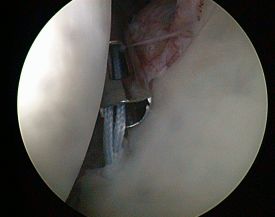

Gelenkspiegelung (Arthroskopie)

HD-Bilder aus dem Schulter- und Kniegelenk

In der Unfallchirurgie der Klinik Bogen kommen neben den herkömmlichen offenen Operationsverfahren insbesondere auch minimal invasive OP-Techniken zum Einsatz. Die sogenannte Schlüsselloch-Chirurgie heißt im Gelenkbereich Arthroskopie oder Gelenkspiegelung.

- zielgenaue Behandlung (gute Sicht dank stark vergrößerter Gelenkdarstellung über HD-Monitor)